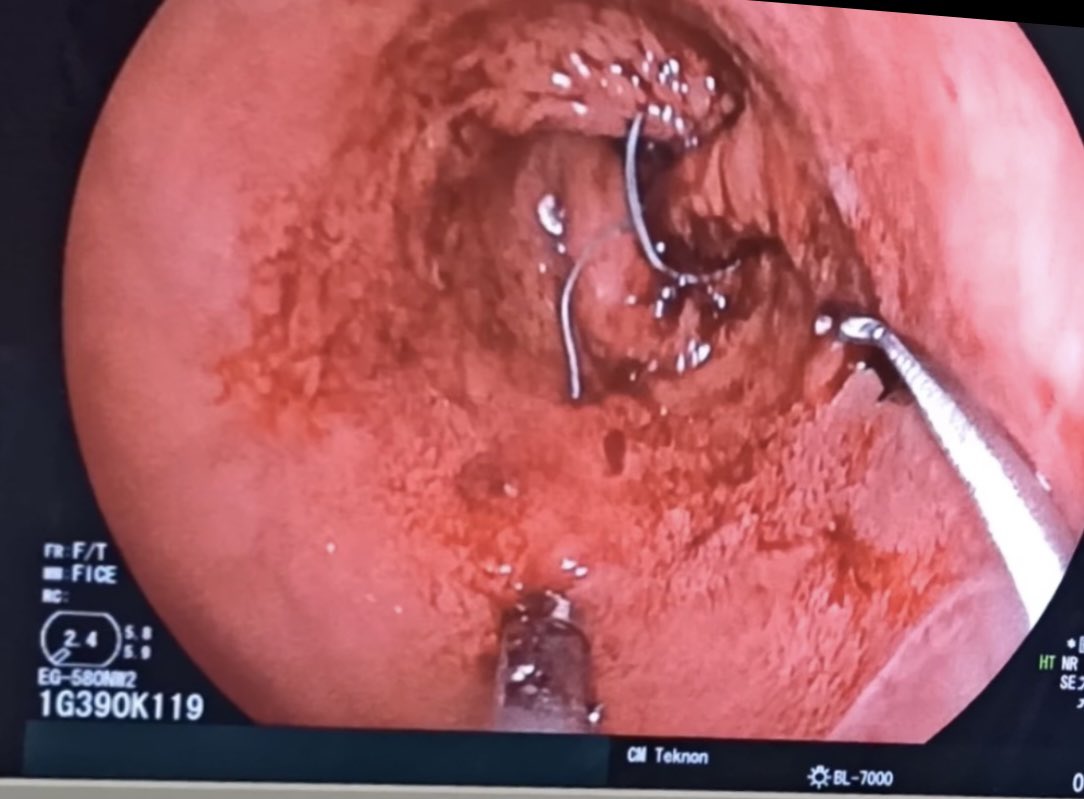

#MedCase 🧓 65 años con ingesta accidental de cuerpo extraño hace 24 horas. Intento fallido de extracción es referida para tratamiento. Endoscopia asistida por cap. Retiro con campaña “artesanal” de Hood. Se observa laceración esofágica y colocación de clips.